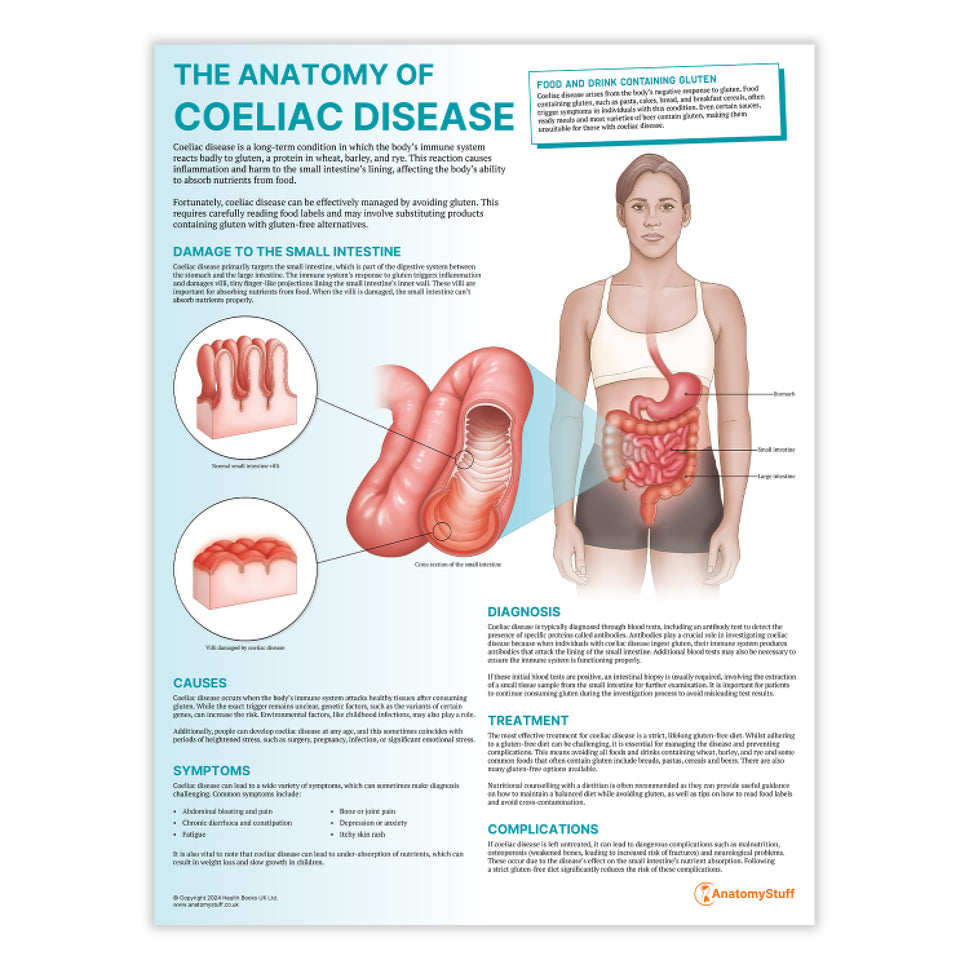

Enhance medical education with our collection of digestive system anatomical models including the stomach, liver, gallbladder, pancreas & colon models. Discover the anatomy of healthy organs as well as common gastrointestinal diseases such as stomach ulcers, gallstones and liver cirrhosis. Our digestive system anatomy posters are ideal for study and patient education.

At AnatomyStuff we stock a diverse range of digestive system anatomical models to suit your training needs. From budget models and affordable medical education posters to highly advanced 3D printed bowel models, you can transform medical training and patient education. As well as our own exclusive collection, we are proud resellers of 3B Scientific, Anatomy Lab, Denoyer-Geppert Science Company, ESP Models, Erler Zimmer and GPI Anatomicals. Explore our exclusive collection of digestive system anatomy charts, posters, fine art prints and digital anatomy study guides. Discover the anatomy of key organs like the liver, stomach, pancreas and bowel as well as the pathophysiology of common conditions like peptic ulcer disease, coeliac disease, IBD and much more. We have anatomy posters suitable for school children all the way up to medical degree level. From a liver anatomy poster to a digital study guide all about common GI disorders, find exactly what you need right here to enhance medical training and patient education.